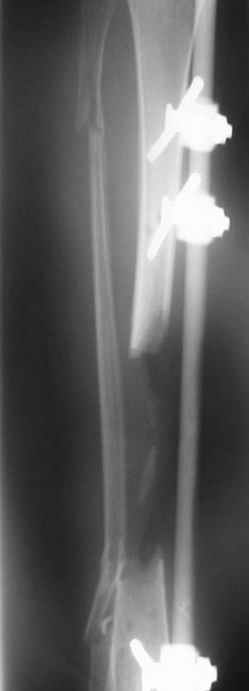

This Patient have to be treated by using Ilizarov bifocal bone transport, aproximatly as showen here.

You can do it like this also...